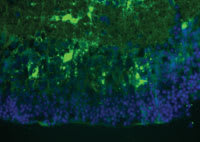

Figure 1. Mice homozygous for a mutation in the Rpe65 gene were transplanted with mouse embryonic stem cells expressing the yellow fluorescent protein (YFP). Immunofluorescence analysis of transplanted eyes showed differentiation of transplanted cells and their incorporation into multiple layers of the host retina. Cross sections of transplanted eyes were stained using a FITC-conjugated antibody against YFP. (40x) |

What do we know about stem cells today? Data exist showing that stem cells can integrate into existing retinal tissue. As seen in Figure 1 in this rodent model, the immunohistochemically fluorescent stem cells are seen to migrate and incorporate to existing retinal tissue. This is 1 of the encouraging findings that suggest our ability to rebuild retinal structure using these multi-potential cells (Figure 1). Cells that have been tested to date include multi-potential embryonic stem cells as well as more differentiated retinal progenitor cells. These cells have mostly been injected into the vitreous cavity and not into the subretinal space. However, it has been described in the past that not all stem cell injections result in integration to existing retinal tissue, and it has been seen that retinal stem cells injected into the vitreous cavity can result in benign tumors of cells adjacent to retinal tissue (Figure 2). In addition, autologous hemopoietic stem cells have been shown to have a positive effect on retinal vasculature and neural sensory retinal thickness, as well as the ability to preserve ERG in treated animals. These animals otherwise will extinguish their ERG without these stem cell injections.9 Stem cells might require specific preparation and biochemical and cellular environments to produce the best stem cells for injection.